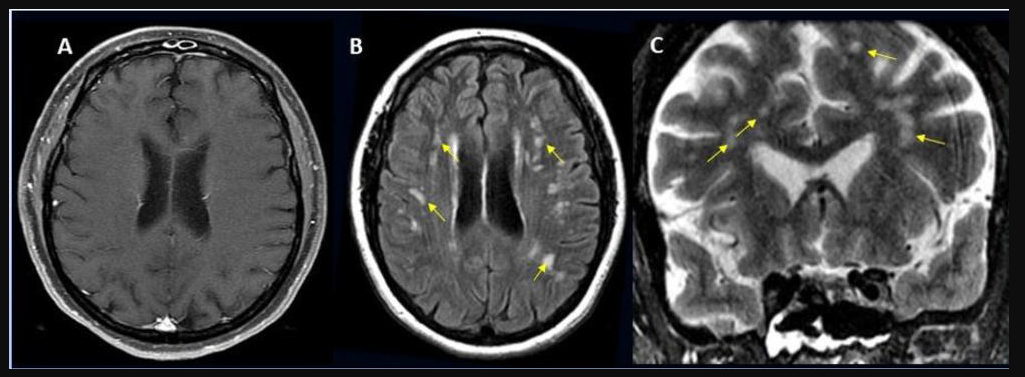

This photo gallery shows the variety of radiological presentations of COVID-19 (SARS-CoV-2) in medical imaging, including computed tomography (CT), radiograph X-rays, ultrasound, echocardiograms and magnetic resonance imaging (MRI). The radiology images show examples of typical COVID pneumonia in the lungs and the numerous complications the virus causes in the body in multiple organs, including the brain, kidneys, heart, abdomen and vascular system.

Ultrasound, especially hand-held ultrasound imaging devices, have become a primary imaging modality for novel coronavirus because of the ease to bag the device and sterilize it after use. CT and mobile X-ray systems are also used as front-line imaging systems for COVID-positive or suspected COVID patients.